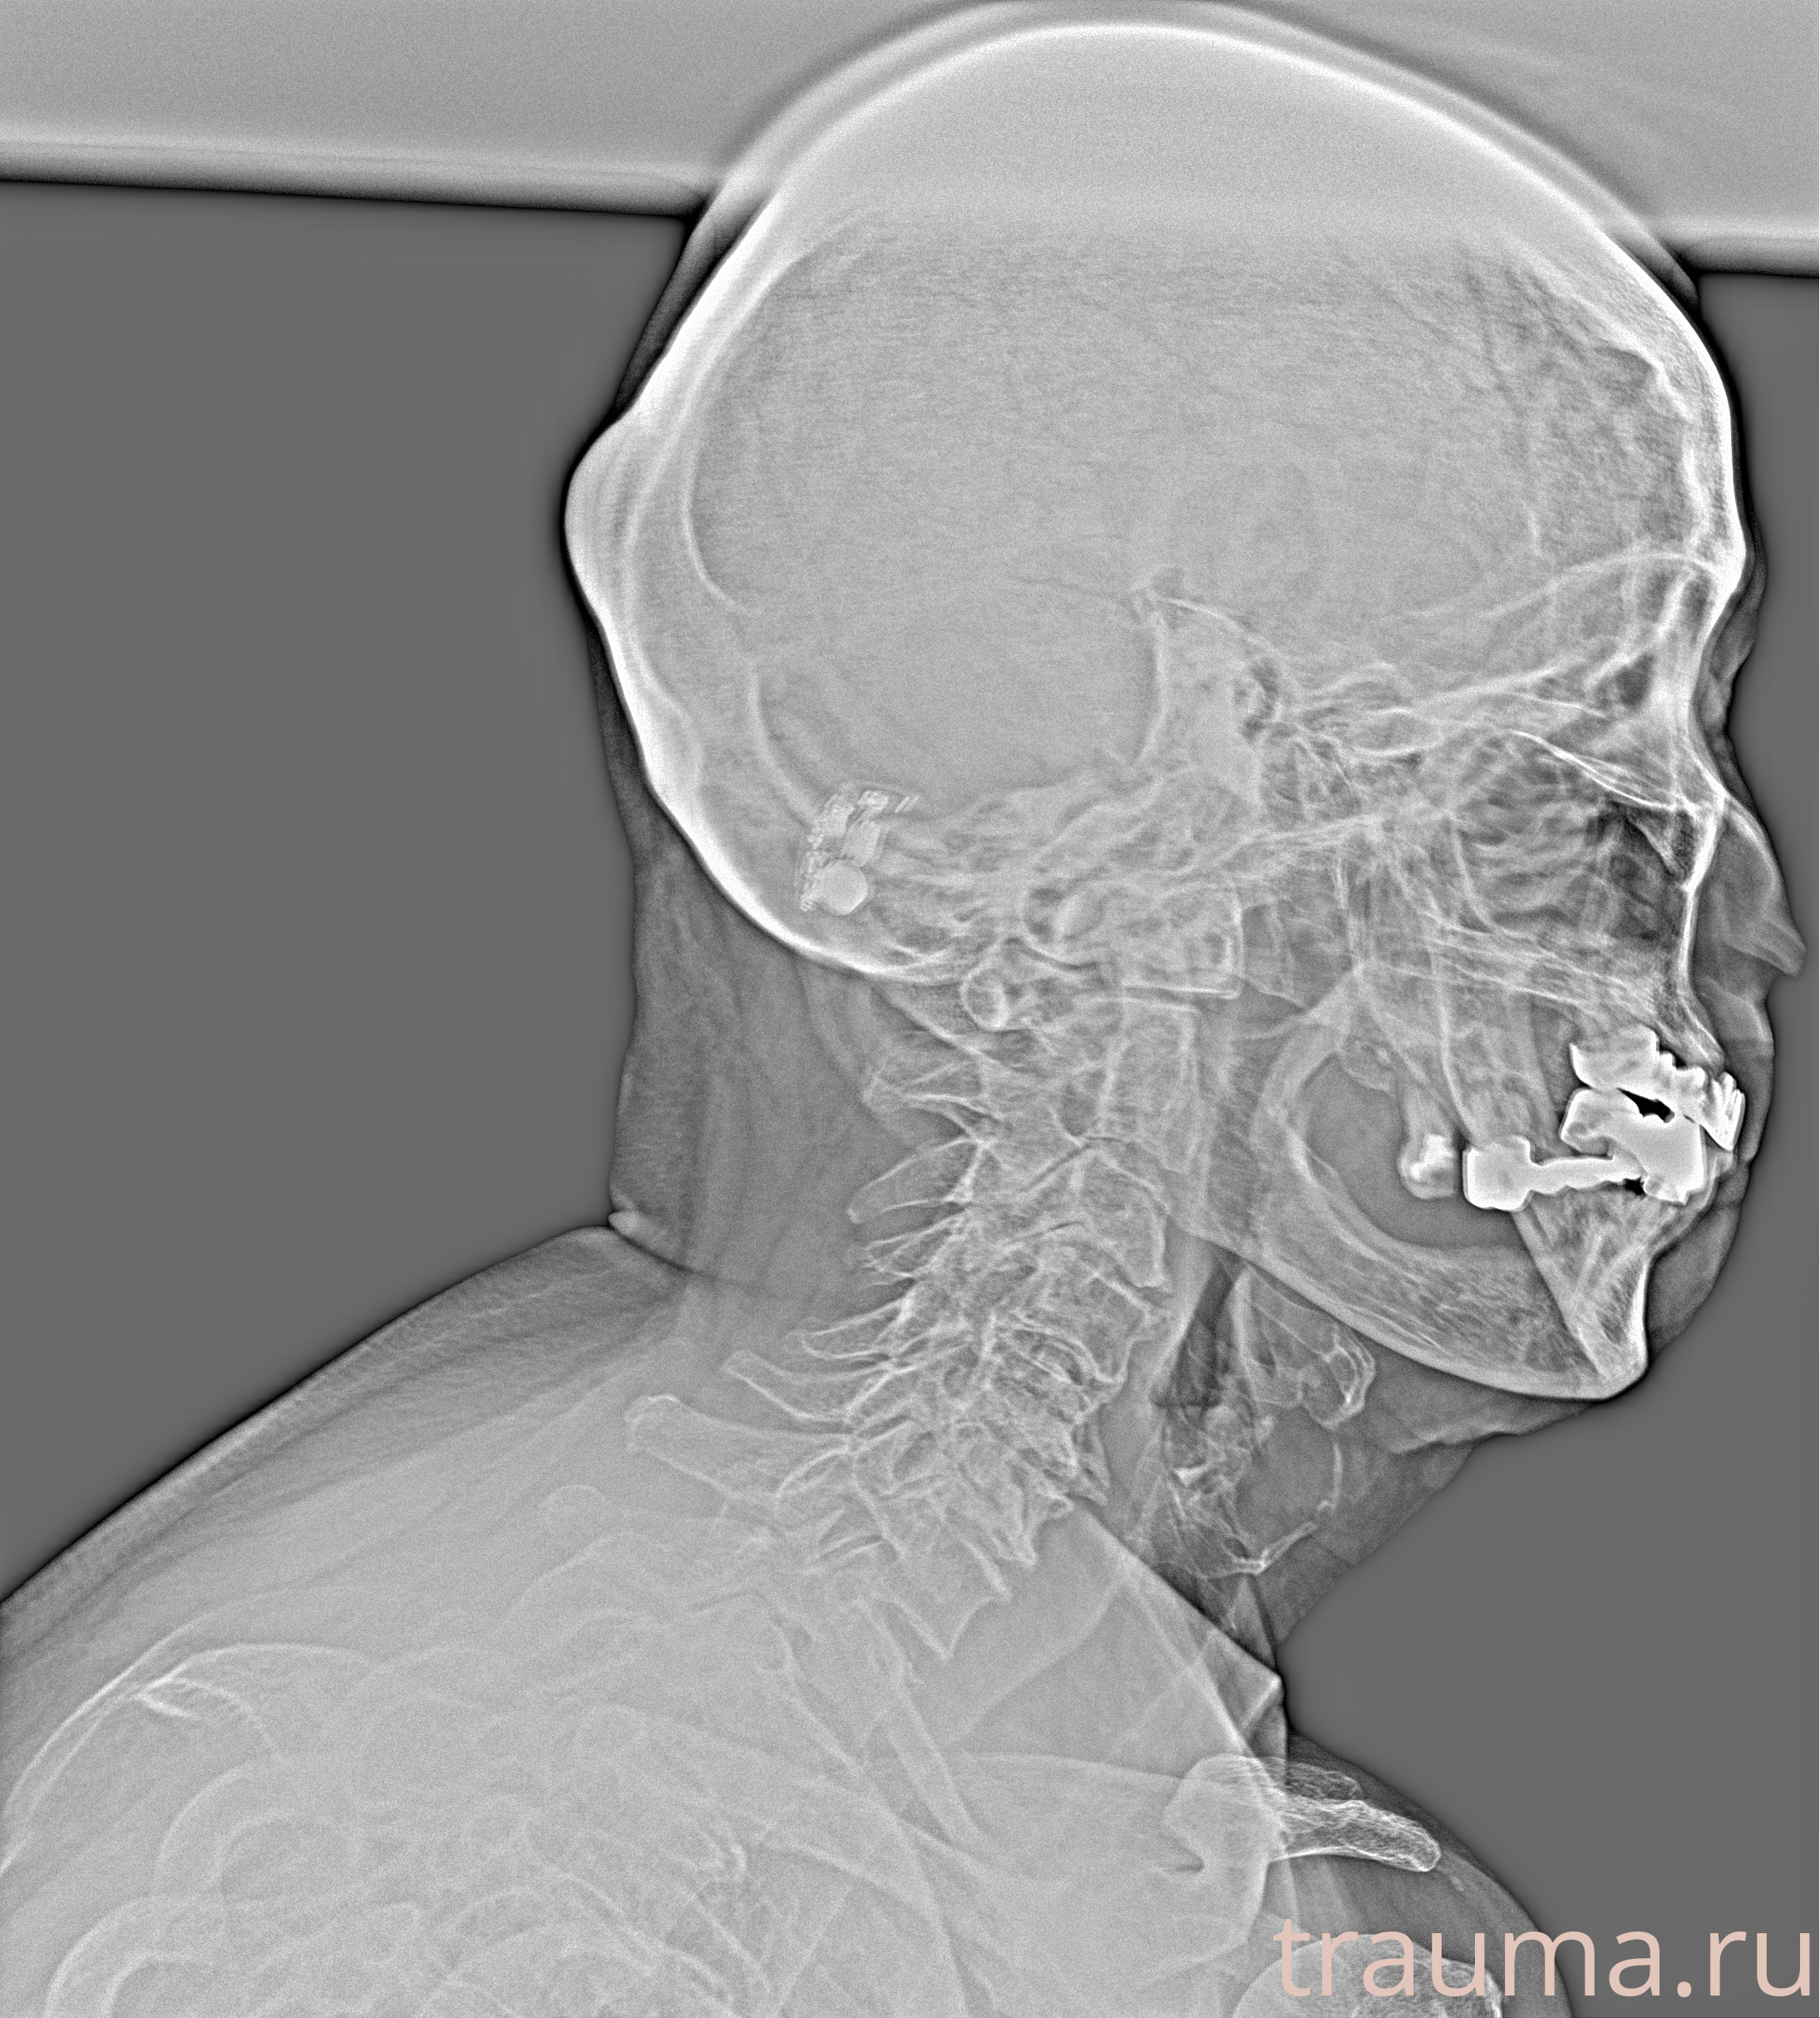

Рентген на дому: по вашему адресу приезжает врач-рентгенолог, травматолог-ортопед с мобильным рентгеновским аппаратом, проводит диагностику травмы или заболевания, делает необходимые рентгенограммы, дает рекомендации по дальнейшему лечению. Получить качественные снимки в домашних условиях возможно благодаря уникальной методике, разработанной МосРентген Центром для института  Склифосовского